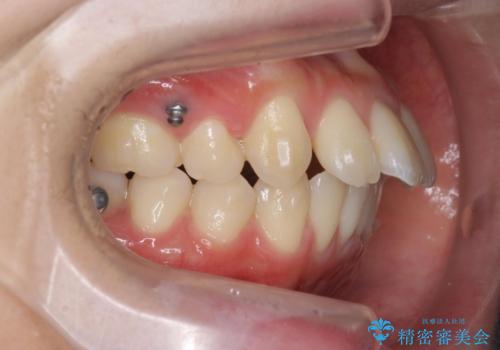

突き出た前歯の改善!マウスピースで再矯正

- 5年前にワイヤー矯正治療を終了したが、突き出たように見える前歯の仕上がりが気に入らず、再矯正治療を希望され来院されました。

マイクロインプラントを用いた遠心移動とIPRを行うことによる前歯の突出感の改善をマウスピース矯正治療で計画します。

突出していた前歯の角度が大きく改善し、審美的な仕上がりに満足いただくことができました。